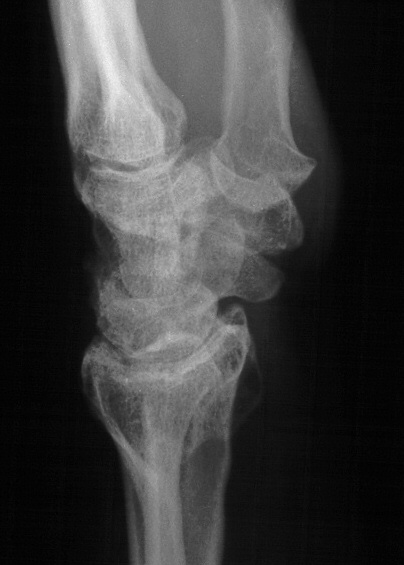

Preop, wrist splint tan line, two years after intraarticular distal radius fracture:

Preoperative Xrays: